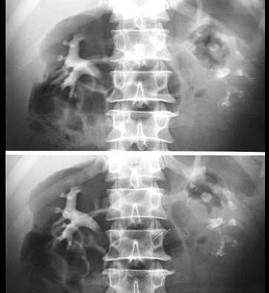

问题 下列有关肾结核影像学检查的说法,正确的有 ( )

选项 A、肾结核广泛破坏肾功能丧失时,IVU不能显示出典型的结核破坏性病变 B、泌尿系统平片见到局限的钙化灶应与肾结石鉴别 C、IVU对肾结核治疗方案的选择必不可少 D、IVU早期表现为肾盏失去杯形,不规则扩大或模糊变形 E、CT对诊断“肾自截”有独特意义

答案 ABC